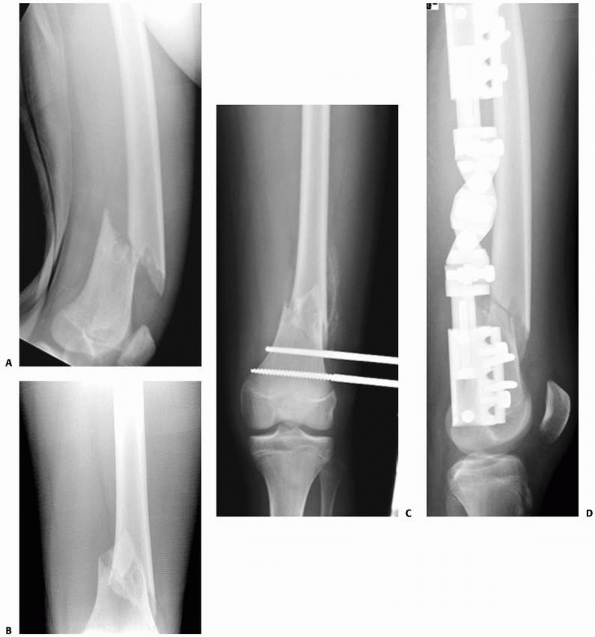

Pathologic fractures may occur in patients with neoplasms, most often

benign lesions such as nonossifying fibroma, aneurysmal bone cyst,

unicameral cyst, or eosinophilic granuloma. Although pathologic femoral

fractures are rare in children, it is essential that the orthopaedist

and radiologist study the initial injury films closely for the subtle

signs of primary lesions predisposing to fracture, particularly in

cases of low-energy injury from running or tripping. X-ray signs of a

pathologic fracture may include mixed lytic-blastic areas disrupting

trabecular architecture, a break in the cortex and periosteal reaction

in malignant lesions such as osteosarcoma, or better-defined sclerotic

borders with an intact cortex seen in benign lesions such as

nonossifying fibroma (Fig. 22-2).

![]() |

FIGURE 22-2 A. Femoral fracture through a poorly demarcated mixed, osteoblastic, osteolytic lesion—an osteosarcoma. B. Sclerotic borders of this lesion in the distal femur are typical of a pathologic fracture through a nonossifying fibroma.